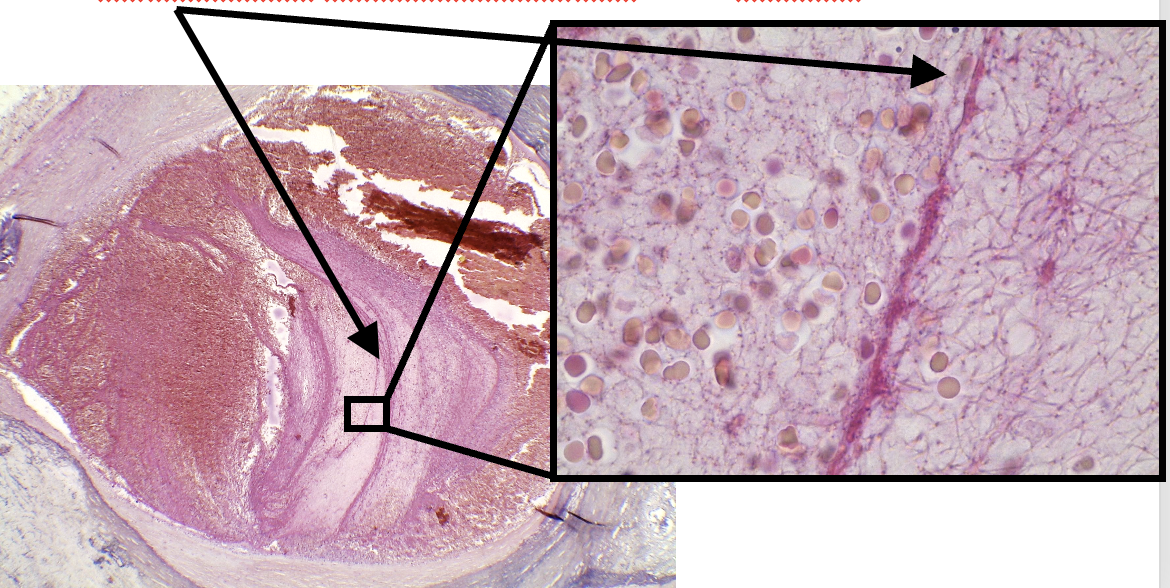

welk preparaat

jichtophus

jichtophus: wat zie je op deze uitvergroting

stapeling van uraatkristallen onder de dermis

Jichtophus: pathologische veranderingen

onder dermis:opstapeling van uraat kristallen (=fijne witte naalden en amorfe hematoxifiele structuren )

inflammatoire reactie: lymfocyten, macrofagen & reuscellen